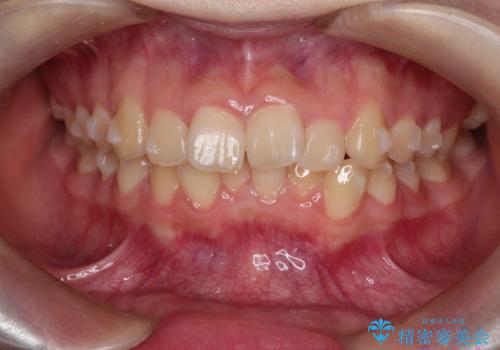

上下の前歯のガタガタを目立たず治したい インビザラインによる見えない矯正

- 上下の前歯のガタガタを治したいとのことで来院されました。

お友達がインビザラインによるマウスピース矯正を行っているとのことで、マウスピースでの治療を希望されました。

上下の歯と歯の間をわずかに削り、並べる計画としました。

上下の正中が一致していませんが、受験を控えているためご本人の希望もあり、いったん終了とさせていただきました。